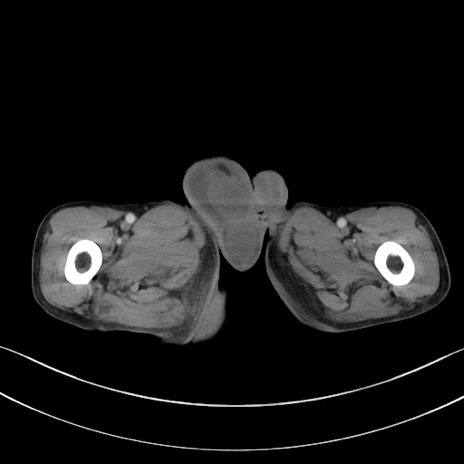

症例3(横断像)

【症例】 70歳代男性

【主訴】右鼠径部腫瘤、疼痛

【現病歴】本日朝より上記主訴あり、受診。

【既往歴】膀胱癌にて膀胱全摘、両側尿管皮膚瘻

【データ】WBC 5600、CRP 0.56